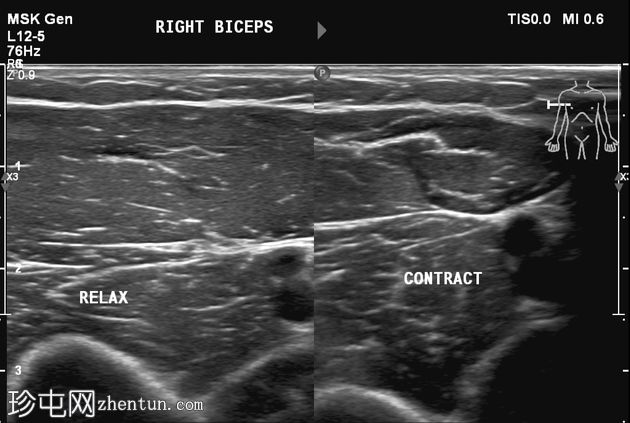

静息状态:肱二头肌短头和长头肌肉结构正常。肌腱和肌腱连接处完整,仅有轻微的断裂或积液迹象。

肘关节屈曲及肌肉收缩动态成像:肱二头肌短头和长头肌纤维之间出现充满液体的裂隙,提示局部肌筋膜分离/拉伤。未见肌纤维全层撕裂。肱二头肌远端止点正常。